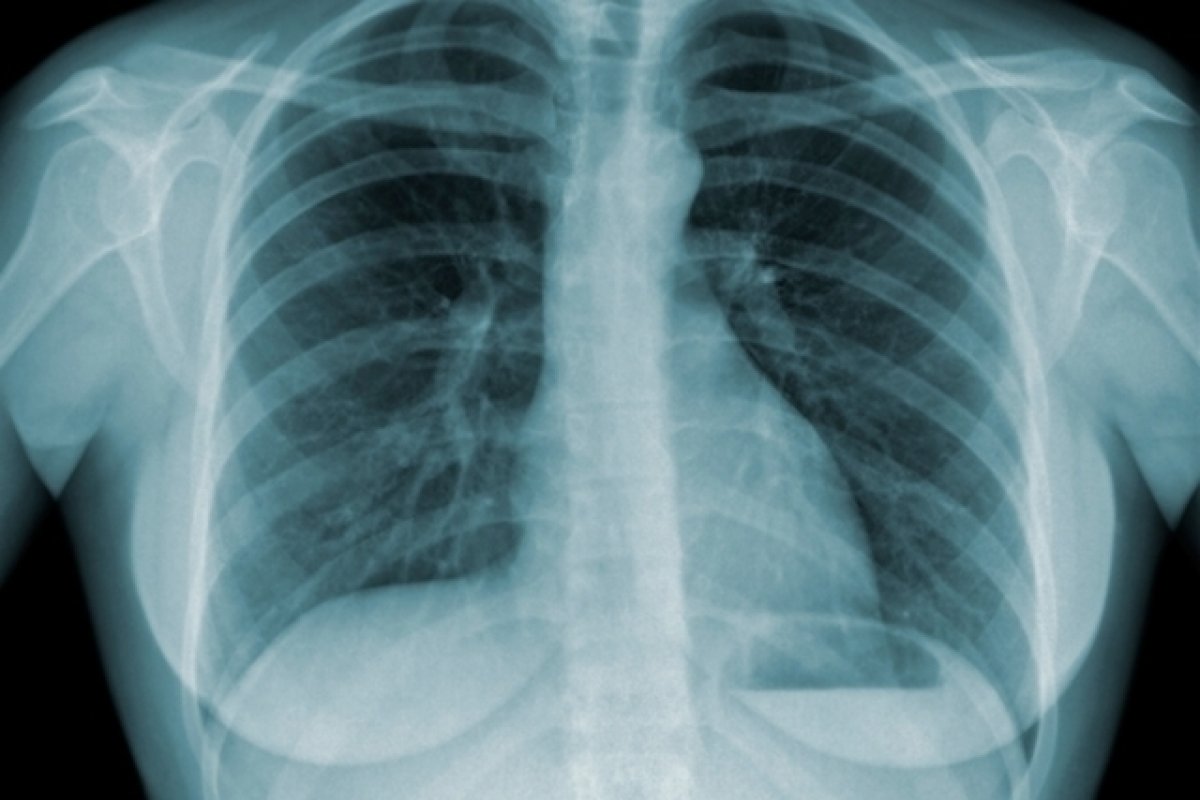

Foto: Reprodução